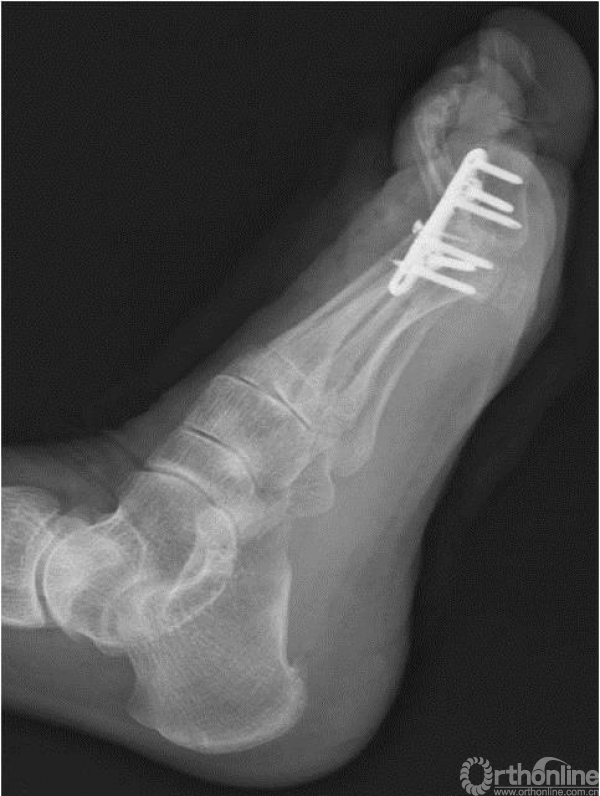

17、 术后X线

四、术后3个月随访